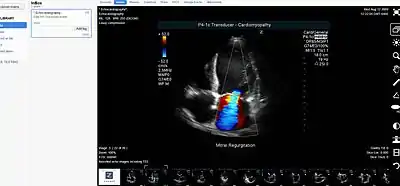

- Picture archiving and communication system (PACS) - A medical imaging technology that provides economical storage of, and convenient access to, images from multiple modalities within a facility.

- DICOM - A standard for handling, storing, printing, and transmitting information in medical imaging.